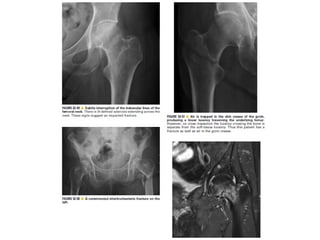

Skeletal trauma was presented by Dr Laith Fadhel with reference to Grainger's Diagnostic Radiology textbook. The presentation covered skeletal trauma as assessed through diagnostic radiology techniques. Key findings and treatments for skeletal injuries were likely discussed.